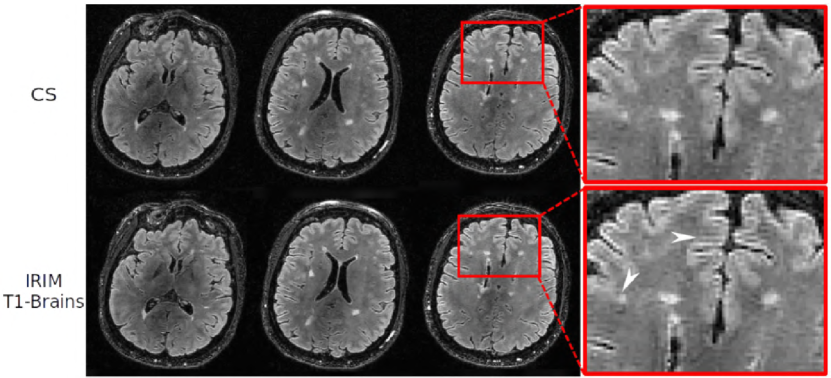

Finally, Fig. 7 shows FLAIR images of an MS patient, reconstructed with the CS and the most efficient model, the IRIM trained on the -weighted brain dataset. Visually, white matter lesions seen in the CS images (here taken as the reference) can also be identified in the IRIM reconstructions. Confirming the simulation experiment, the IRIM slightly enhanced the signal compared to CS. This is visible both in the lesion as well as in the minute cortical gyrus texture amplification (see arrows).